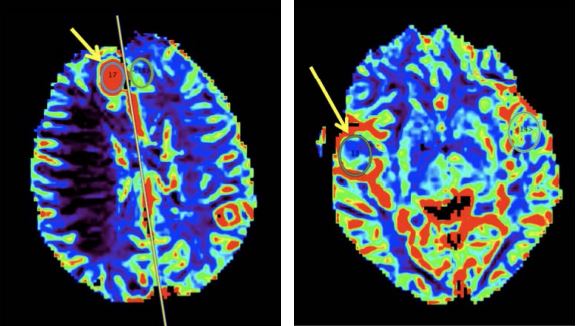

Перфузійно-зважені МРТ-зображення були оброблені за допомогою пакета Olea Sphere® (Olea Medical®) для відображення карт об'єму мозкової крові та K2 (проникність). Були визначені області інтересу і оцінені відповідні перфузійні карти.

Об’єм мозкової крові: Об’єм мозкової крові підвищений при парафакторіальному ураженні (зліва), тоді як при лобово-очноямковому ураженні він є нормальним (справа). Значне підвищення CBV в парафасціальному ураженні зумовлене пухлинною гіперваскуляризацією. Навпаки, у фронто-оперкулярному ураженні кровонаповнення еквівалентне нормальній паренхімі і дещо знижене в периферійних ділянках ураження (на карті позначено зеленим кольором).

Значення пухлини: 4.01Значення пухлини: 1.29

Нормальне/референтне значення: 1.25Нормальне/референтне значення: 1.47

Відношення: 3.21Відношення: 0.87

K2: Карти проникності показують підвищений рівень K2 в обох ділянках ураження. Обидва ураження мають підвищену капілярну проникність.

Значення пухлини: 182.48Значення пухлини: 122.98

Нормальне/референтне значення: 28.57Нормальне/референтне значення: 58.97

Відношення: 6.39Відношення: 2.09

Криві концентрації контрастної речовини

Синя крива: (темна і світла): референтні показники поля обзору (нормальна тканина)

Червона крива: поле обзору в межах парафалькоріального ураження.

Збільшення площі під кривою пояснюється збільшенням об’ємом мозкової крові. Крива ширша, а значення під базовою лінією є типовими для менінгіоми.

Зелена крива: поле обзору в межах лобно-очноямкового ураження.

Площа під кривою в нормі, але значення вище базової лінії характерні для первинної церебральної злоякісної лімфоми.